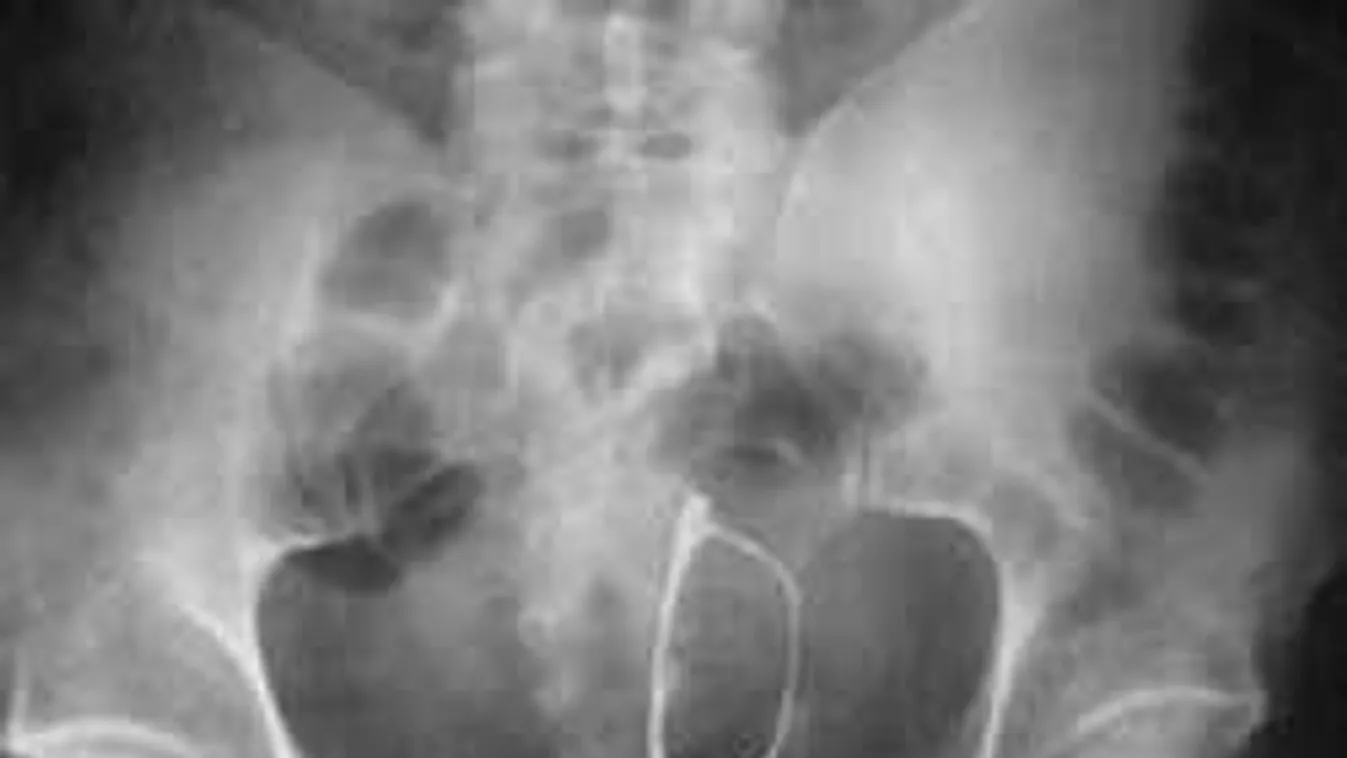

6. A poharat pedig végképp nem értjük. Sem fejjel felfelé, sem fejjel lefelé. Nem, nem és kész.

![]()